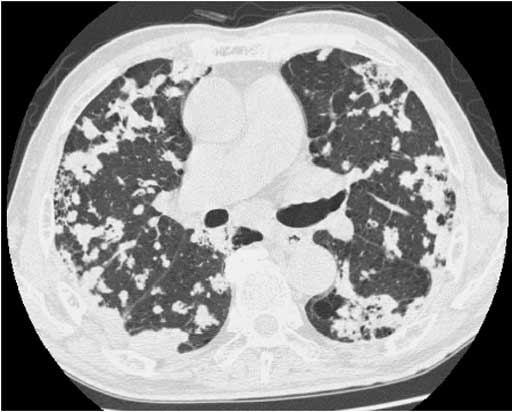

図2 Thin-slice CT1 図3 Thin-slice CT 2

図3 Thin-slice CT 2 図4 Thin-slice CT 3